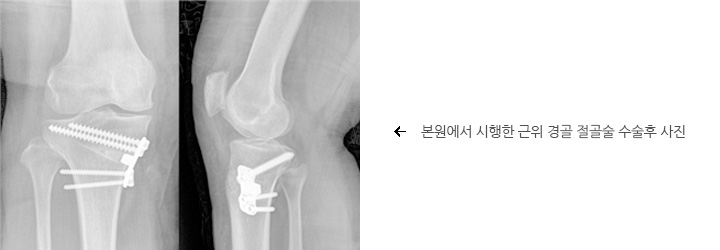

무릎 관절염 : 근위 경골 절골술

무릎 절골술은 60-65세 이하의 젊고 활동적인 환자에서 내측 관절면에 손상이 존재하는 경우 권유되는 수술 방법입니다. 이 수술 방법은 연골의 재생을 촉진 시킬 수도 있습니다. 무릎의 정렬을 회복시키기 위해 뼈를 재정열하여 체중부하 선을 손상되지 않은 부위로 재정렬 시킴으로써 손상된 부위에 압력을 줄여 통증을 완화시키는 원리입니다.체중부하 선을 아프지 않은 쪽으로 옮기는 수술법입니다.

절골술은 무릎의 기능을 향상시키고 관절염으로 인한 통증을 감소시키며 연골의 재생을 도모합니다. 절골술이 기능의 향상과 통증을 감소시키고, 수술 후 자기 관절을 이용하여 활동하게 되므로 활동성이 많은 환자에 유용하며 최근 보고에 의하면 10년 수술 생존율이 90%이상으로 알려져 있습니다.

무릎 관절염은 한 구획을 침범하는 경우가 많으며 대부분 내측입니다. 이런 경우 하지의 정열을 재조정함으로써 체중부하를 아프지 않은 쪽으로 옮겨서 동통을 줄이는 방법으로 근위 경골 절골술이 있습니다.

수술 방법

개방형 근위 경골 절골술은 경골의 내측에서 절골술을 시행하여 변형이 필요한 만큼 개방시킨 후 금속물로 고정하며 벌어진 사이는 골 이식을 시행하게 됩니다. 개방 경골 근위 절골술은 무릎 내측에 절개를 가하게 되고 절골술을 완료하고 나면 절골면을 따라 필요한 만큼 절골 틈을 벌리고 이 틈은 골반에서 이식 골(자가 혹은 타가 골)을 재취하여 삽입한 후 금속판을 이용하여 고정하게 됩니다.

재활

수술 후 통증이 완화되고 관절 운동이 시간이 지남에 따라 호전되면 약 1-2달간의 목발이나 보행기를 이용한 걷기 운동을 권유하게 됩니다. 절골술 후 회복되는 기간은 최소한 3개월의 시간이 필요합니다. 개방 절골술을 시행한 경우 골 이식편이 치유되는 시간 동안수술 부위를 보호를 해야 합니다. 약 6-8주 후에 엑스레이를 통해 이식편이 안정적으로 안착이 되면 체중부하를 시작하며 근력 강화 등 재활운동을 시작하게 됩니다.